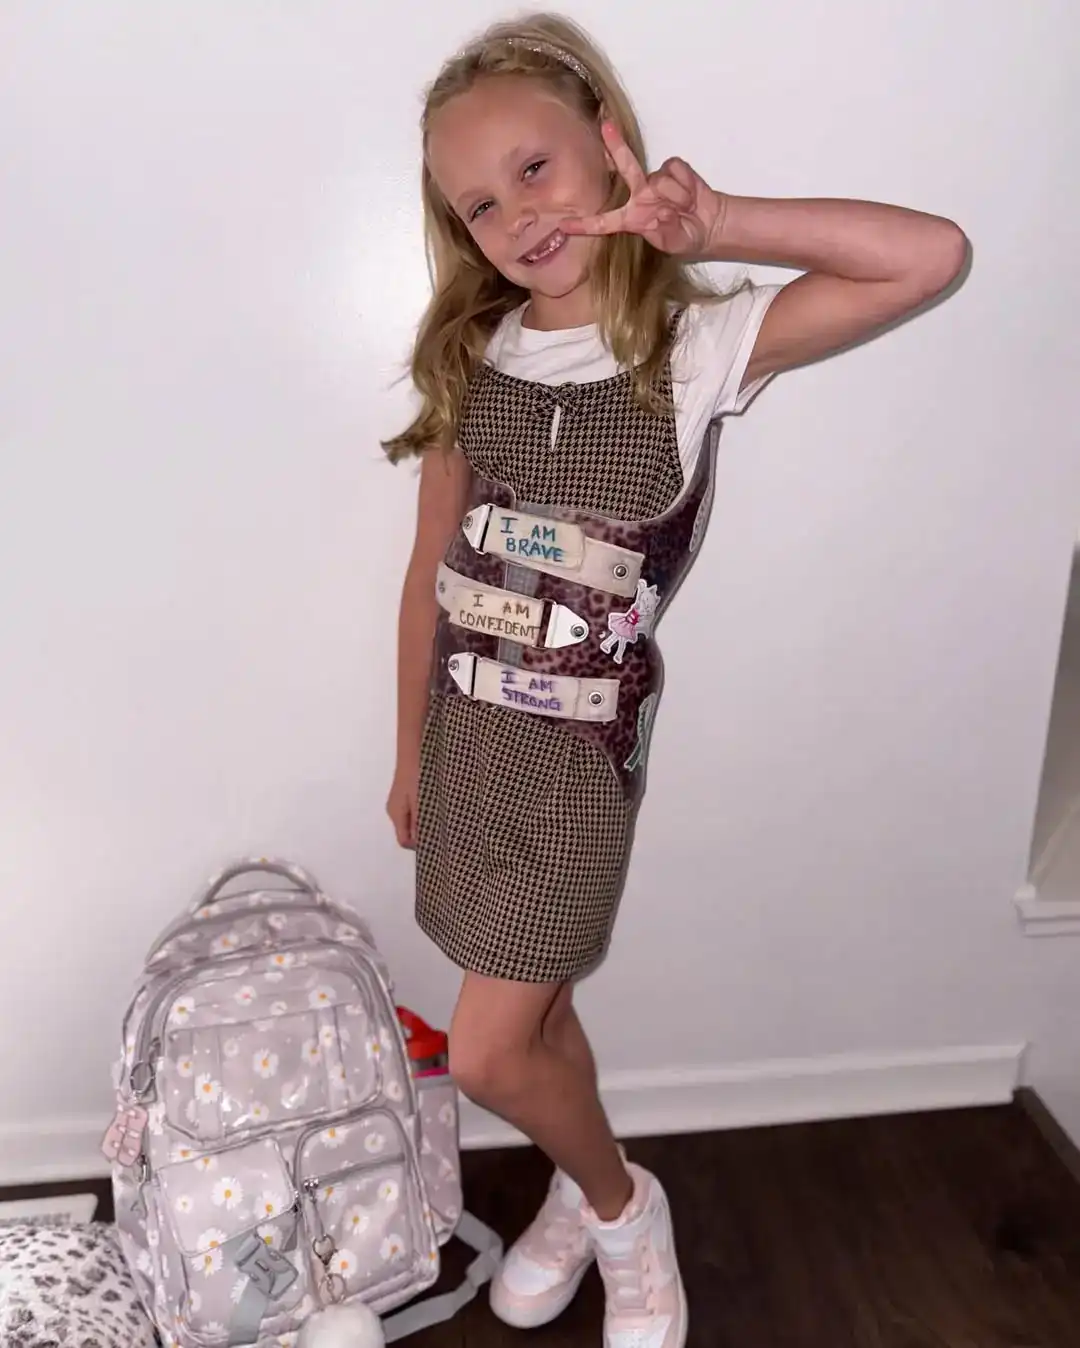

Para Preslee, o tratamento poderia ter sido motivo de insegurança, mas virou um espaço de autoestima. Ela escolheu um colete estampado com oncinha e, junto da mãe, passou a decorar o acessório com desenhos, frases e adesivos. Entre eles, está a sua mensagem favorita e que resume sua força: “Um pouco torta, mas nunca quebrada”.

“Queria que ela tivesse sempre um lembrete de que é incrível, confiante, corajosa e forte. Depois, ela mesma começou a criar suas afirmações e colar adesivos. É o colete dela, e ela usa todos os dias”, contou Thais.

Na escola, a adaptação foi acolhedora. Professores e colegas apoiaram a menina, que chegou a ouvir de amigos que o colete era “legal” e que eles também gostariam de ter um. Em locais públicos, quando há curiosidade, Preslee responde: “Tenho uma curvinha nas costas e uso isso para ficar saudável e forte”.

Os exames mais recentes mostraram melhora das curvas, e a família segue confiante. Para Thais, a forma como a filha encara os desafios é uma lição diária. “Não entendo como uma menina de 7 anos pode ter tanta compaixão, bondade e coração. Ela me inspira todos os dias. Se eu puder proteger essa positividade e mantê-la viva, é isso que mais importa”, finalizou.